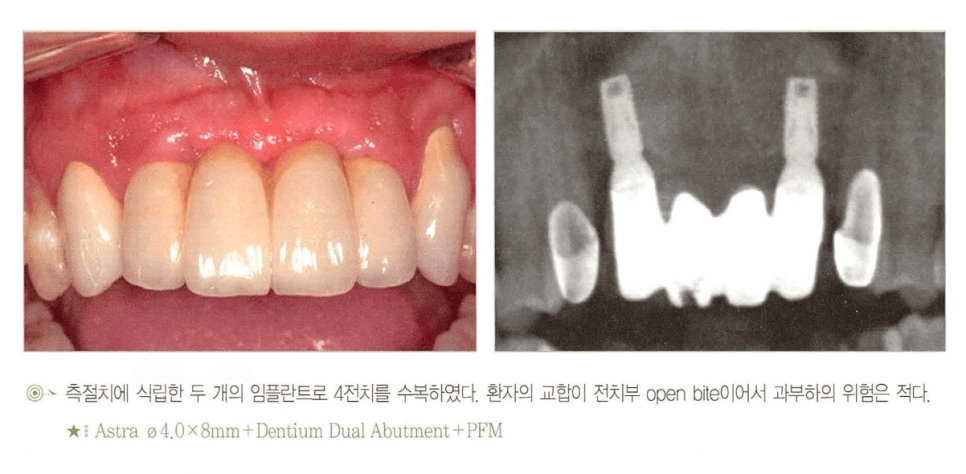

상·하악 전치부 4개 상실

[그림 4] 전치부 open bite 환자에서 측절치에 임플란트 2개를 식립하고 중절치 2개를 pontic으로 연결해 교정적으로 수복한 증례.

- 상악 4전치 — 임플란트 2개(보통 양측 측절치 위치)로 충분한 경우가 많습니다. 중절치와 측절치 한쪽 조합 + 반대측 캔틸레버 설계도 흔히 사용됩니다.

- 하악 4전치 — 하악 전치부는 구강 내에서 골질이 가장 단단한 영역이므로 여유가 있습니다. 임플란트 2~3개로 pontic을 포함한 4-unit 수복이 일반적입니다.